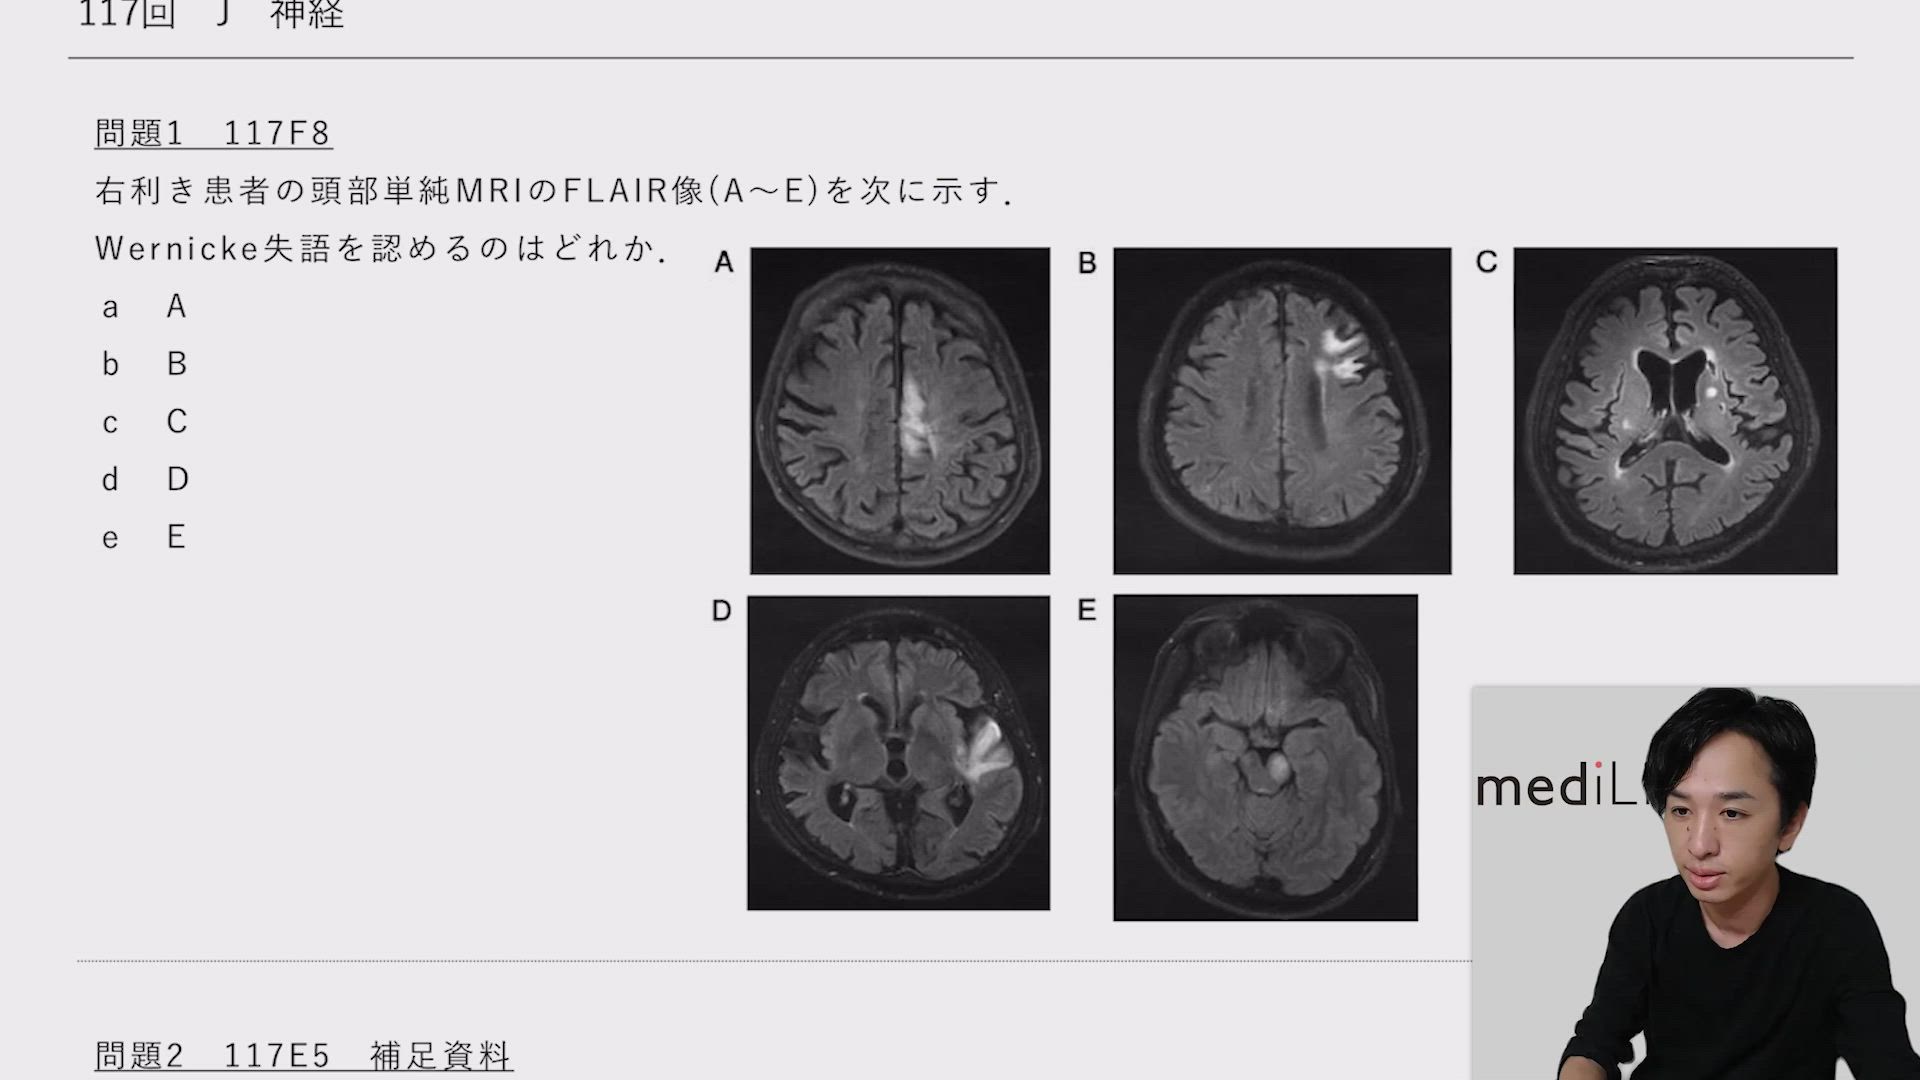

J 神経(117回)

医学